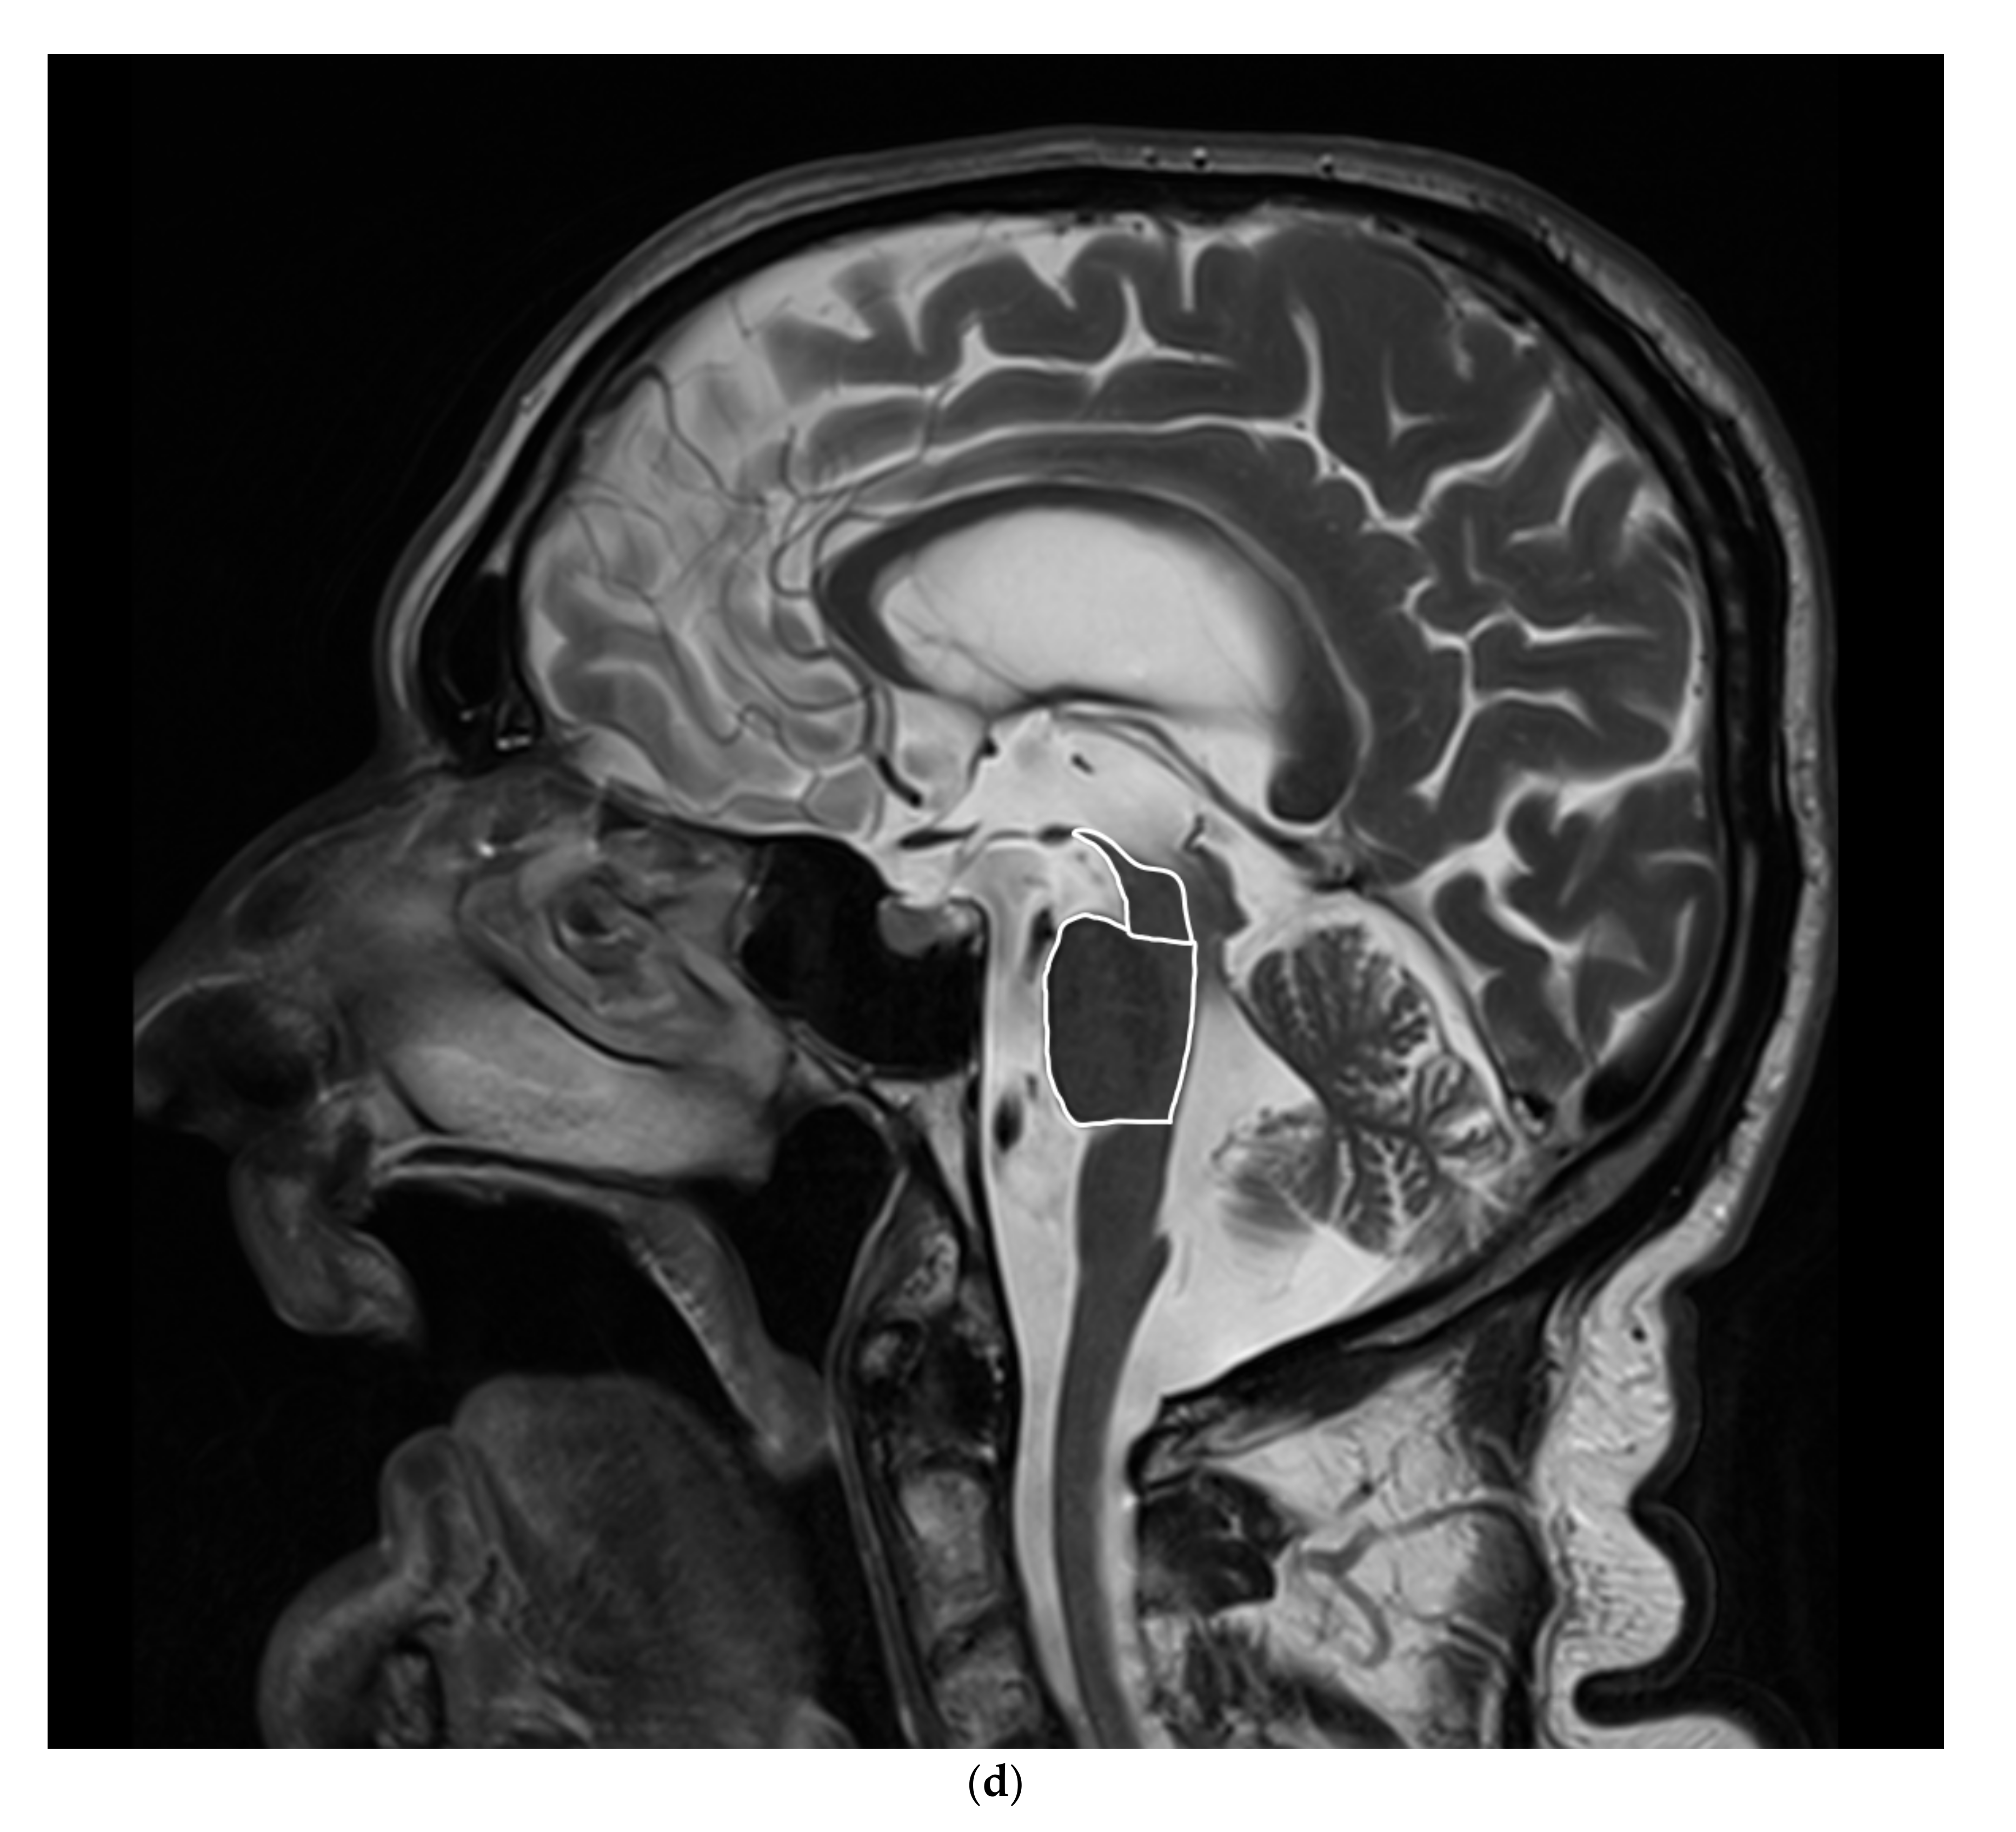

There was a significantly smaller midbrain surface in patients with PSP-P in comparison with patients with MSA–P, 0.76 cm2 vs. 1.08 cm2. Moreover, the ratio of midbrain to pons (M/P ratio) was also significantly smaller in patients with PSP-P vs. MSA-P 0.16 vs. 0.23, but the MRPI values were higher in patients with PSP-P vs. MSA-P 18.75 vs. 10.6 (Table 1 and Table 2) (Figure 1a–d).

Figure 1.

(a). Scatterplot presenting the significant differences between MSA-P and PSP-P in the midbrain surface, (b) Scatterplot presenting the significant differences between MSA-P and PSP-P in the M/P ratio, (c) Scatterplot presenting the significant differences between MSA-P and PSP-P in the MRPI, (d) The atrophy of the mesencephalon in the MRI of a patient with PSP-P.